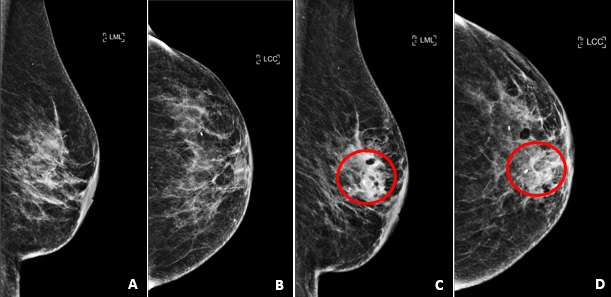

On mammogram, hematomas appear similar to other fluid collections and most commonly appear as a well-defined mass or region of increased density. Borders may be well circumscribed or ill-defined depending on acuity of the hematoma and the integrity of the surrounding tissue. In areas of chronic hematoma, small calcium deposits may develop and evolve into areas of fat necrosis. Similar to seromas, during compression a hematoma may change in shape on mammograms.